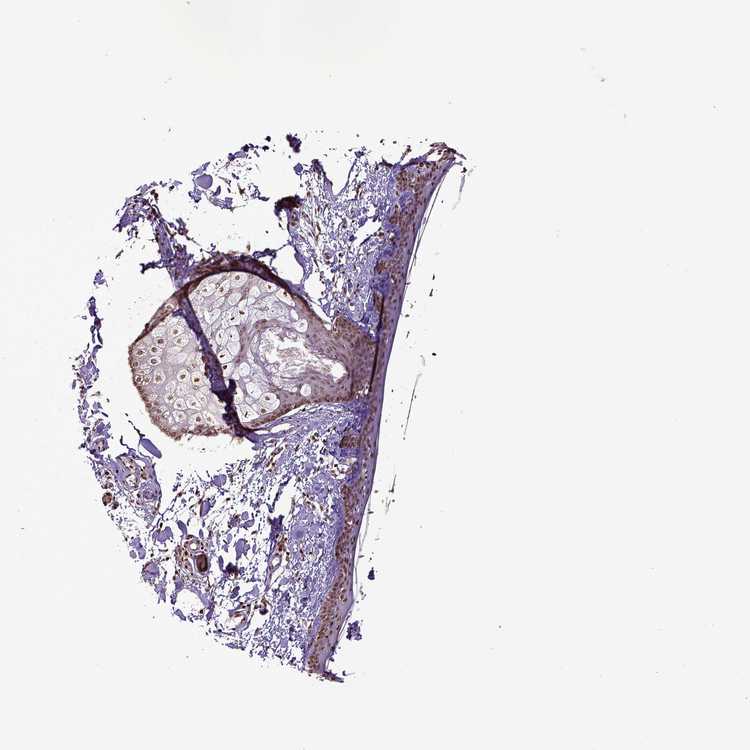

SKIN 2 - Antibody stainingi

Antibody staining in the annotated cell types in the current human tissue is reported as not detected, low, medium, or high, based on conventional immunohistochemistry profiling in selected tissues. This score is based on the combination of the staining intensity and fraction of stained cells.

Each image is clickable and will lead to virtual microscopy that enables deeper exploration of all samples and also displays staining intensity scores, fraction scores and subcellular localization as well as patient and tissue information for each sample.

Antibody HPA004705

Epidermal cells Medium